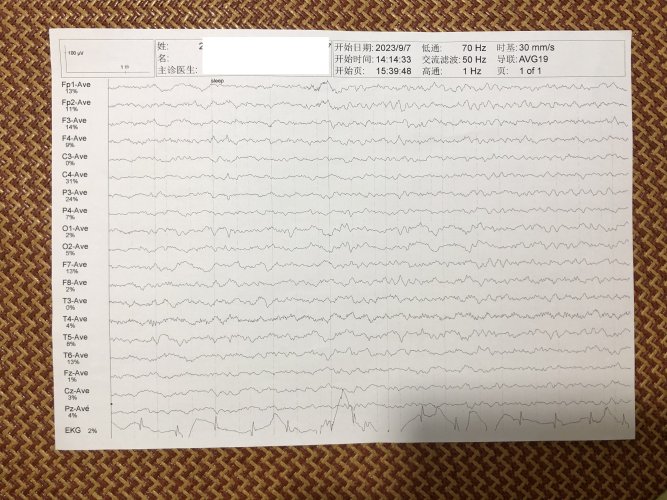

反馈下情况,孩子在国内的医院已经进行过一轮全面检测,没发现什么问题,但是现象是存在的。医生也没什么办法。医生说核磁共振和脑电图没问题,我们也不是很看得懂,各位如果懂的,请指点一下。另外进行了部分基因检测,没发现异常。下一步,我们国庆后打算去更权威的医院去碰碰运气。谢谢各位!

513.6 KB 查看: 103

532.8 KB 查看: 142

551 KB 查看: 132

526.8 KB 查看: 133

510 KB 查看: 103

506.4 KB 查看: 124

495.7 KB 查看: 165

435.1 KB 查看: 151